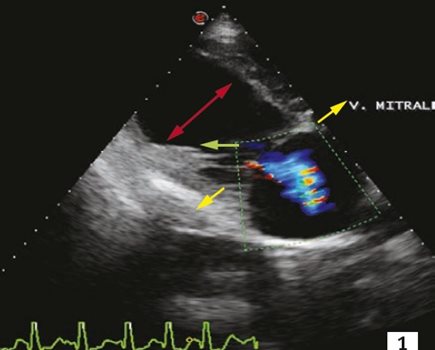

Image 1 Insuffisance mitrale fonctionnelle par dilatation de l’anneau mitral chez un chien atteint de cardiomyopathie dilatée (coupe grand axe quatre cavités par abord droit, mode Doppler couleur). Lors de cardiomyopathie dilatée, l’augmentation du volume télédiastolique dilate l’anneau mitral (flèches jaunes), écarte les piliers (flèche rouge) et exerce une traction excessive sur les cordages (flèche verte). Cette traction retient les feuillets valvulaires sous le plan de l’anneau mitral. Les feuillets ne coaptent plus et la valve fuit.

Le tableau clinique des CMD de forme classique est dominé par des signes congestifs : intolérance à l’effort, toux, dyspnée, épanchements. Un souffle cardiaque systolique apexien gauche d’origine fonctionnelle (dilatation de l’anneau mitral) est présent (photo 1). Les troubles du rythme supraventriculaire sont fréquents : fibrillation atriale, extrasystoles. Des troubles ventriculaires sont également présents (extrasystoles, tachycardie).